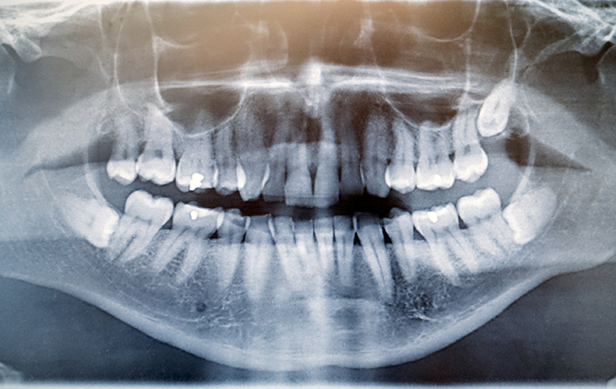

Our team can keep an eye on your wisdom teeth, even before they’ve erupted through the gumline, at each of your checkups and let you know when and if they need to be extracted. If your wisdom teeth are at risk of compromising your oral health or impacting your comfort, we can schedule a wisdom tooth extraction in Hartwell for you. Call our office today to learn more or schedule an examination.

Before we schedule a wisdom tooth extraction procedure for any of our patients, we do a consultation first. During your consultation, we’ll examine diagnostic images of your mouth and speak with you about your symptoms. If we determine that your wisdom teeth need to be removed but they’re still impacted below the gumline, a surgical extraction may be necessary. This involves our team creating a small window in the gumline that will allow us to access the impacted tooth, divide it up into smaller pieces, and remove each of the pieces. However, if the wisdom teeth have erupted, we can complete a simple extraction by lifting them out of their sockets.